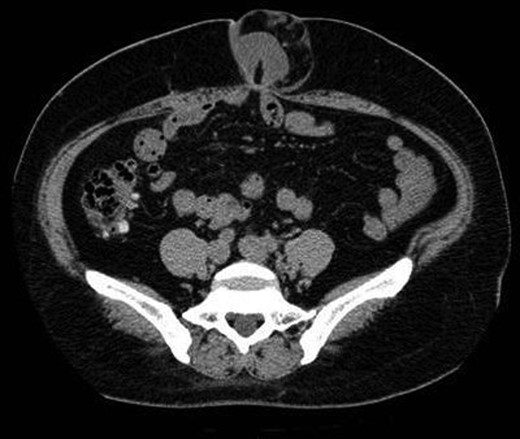

A 42-year-old woman developed an umbilical hernia and left it untreated. Three years later, she was admitted to the emergency room at our hospital with incarceration of the umbilical hernia. The hernia had a size comparable to that of a tennis ball. The patient weighed 75 kg and had a height of 140 cm. Her body mass index (BMI) was 38.3 kg/m2, which is categorized as obese. Computed tomography imaging showed an umbilical hernia with an incarcerated portion of small intestine and a hernial orifice of ∼2 cm (Fig. 1). A gentle attempt at reducing the hernia was unsuccessful; therefore, we decided to perform an emergency operation. After the induction of general anesthesia using a muscle relaxant agent, the hernia was reduced. A 12-mm trocar was inserted just below the epigastric region, and pneumoperitoneum was established by insufflation with carbon dioxide to a 10-mmHg abdominal pressure. Two 5-mm trocars were placed in the right and left lateral abdominal region, respectively. On laparoscopic examination of the abdominal cavity, we identified the portion of incarcerated small intestine. It was reddish and congested; however, there was no evidence of necrosis or perforation (Fig. 2A, arrows). The size of the umbilical hernial orifice was ∼2 × 2 cm (Fig. 2B). We selected a 12 × 12 cm composite mesh (Composix™, DAVOL, Inc., Subsidiary of C. R. Bard, Inc., Warwick, RI, USA) to cover the hernial defect by at least 5 cm in all directions. The composite mesh was inserted through the 12-mm trocar, and it was fixed to the abdominal wall circumferentially by a permanent fixation system (PermaFix™, DAVOL, Inc., Subsidiary of C. R. Bard, Inc.; Fig. 2C). The surgical procedure was uneventful and the total operation time was 112 min. The patient recovered uneventfully and was discharged on postoperative day 9. She remains free of recurrence 20 months after surgery.

A computed tomographic scan showing the umbilical hernia and an incarcerated portion of the small intestine. The size of the hernial orifice was ∼2 cm.